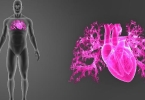

• 心脏血管畸形的症状

心脏血管畸形的症状

心脏血管畸形的症状需立即就医,常见表现包括紫绀、呼吸困难、喂养困难、发育迟缓和反复呼吸道感染。1、紫绀:紫绀是心脏血管畸形的典型症状,由于血液中氧含量不足导致皮肤、嘴唇或指甲床呈现青紫色。治疗方法需根 ...